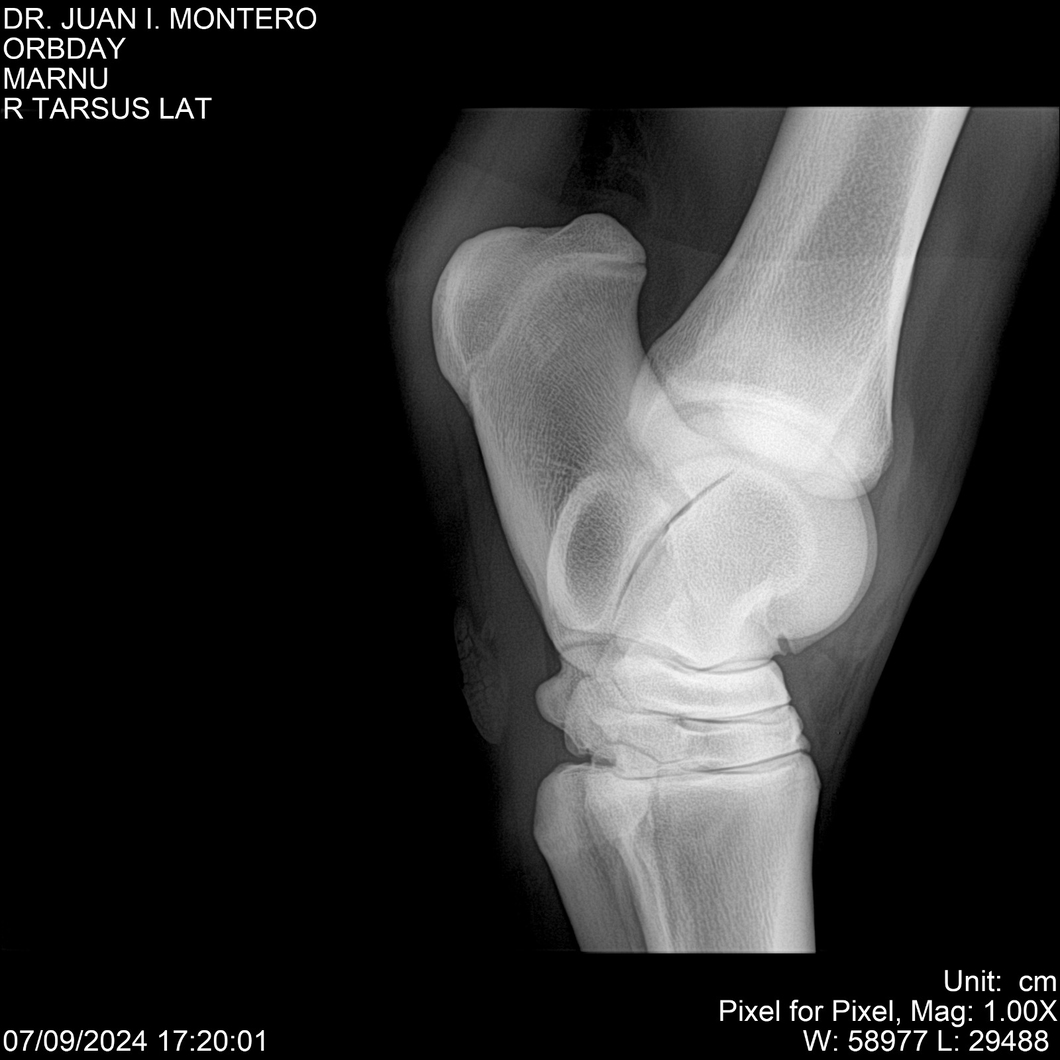

Visualizaciones